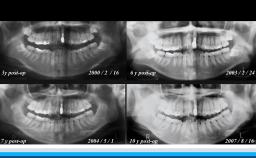

インプラントはQOLと全身の健康状態を向上させる選択肢である

高齢者の咬合力回復は,栄養摂取や全身の筋力維持に貢献できる.インプラント治療もQOL向上に大きく寄与できる可能性を有する.一方,術後の全身の健康状態の変化に対応したメンテナンスを術前から考える必要がある.

• Long-Term Data

• Outcomes